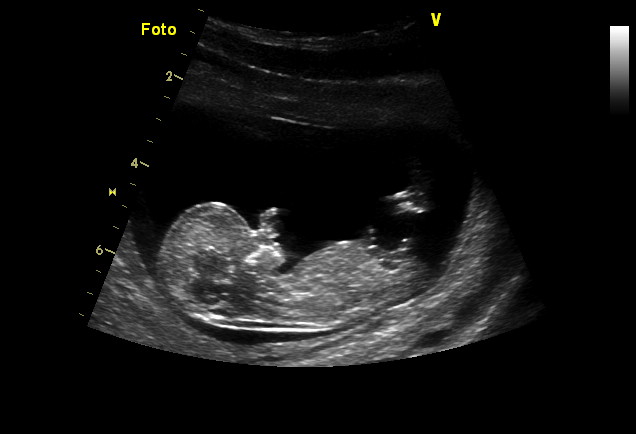

zajtra velke UTZ v 21. tyzdni

NT screening dneska vyšiel fantasticky, som v 13tt a malé meria 5,5cm